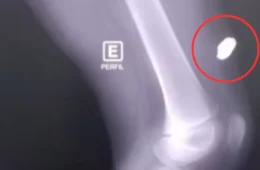

Rafael passava pela rua no momento dos tiros e acabou atingido com uma bala perdida na cabeça, segundo informações de policiais militares da 27ª Companhia Interativa Comunitária (Cicom).